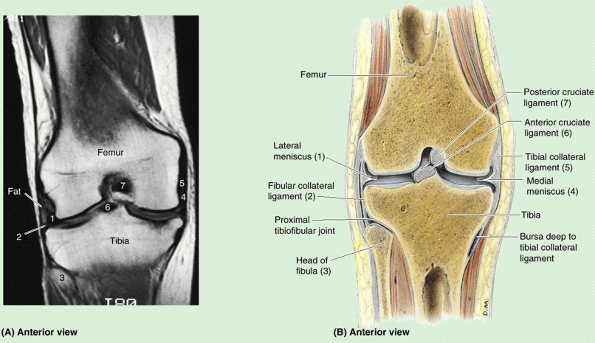

Knee (L. genu) or knee region (L. regio genus). This part/region includes the prominences (condyles) of the distal femur and proximal tibia, the head of the fibula, and the patella (knee cap, which lies anterior to the distal end of the femur) as well as the joints between these bony structures. The posterior part of the knee (L. poples) includes a well-defined, fat-filled hollow, transmitting neurovascular structures, called the popliteal fossa.

femoral condyles articulate with menisci (crescentic plates of

cartilage) and tibial condyles to form the knee joint (Fig. 5.4).

The menisci and tibial condyles glide as a unit across the inferior and

posterior aspects of the femoral condyles during flexion and extension.

The convexity of the articular surface of the condyles increases as it

descends the anterior surface, covering the inferior end, and then

ascends posteriorly. The condyles are separated posteriorly and

inferiorly by an intercondylar fossa (intercondylar notch) but merge anteriorly, forming a shallow longitudinal depression, the patellar surface (Fig. 5.7), which articulates with the patella. The lateral surface of the lateral condyle has a central projection called the lateral epicondyle. The medial surface of the medial condyle has a larger and more prominent medial epicondyle, superior to which another elevation, the adductor tubercle,

forms in relation to a tendon attachment. The epicondyles provide

proximal attachment for the collateral ligaments of the knee joint.

separated by an intercondylar eminence formed by two intercondylar tubercles (medial and lateral) flanked by relatively rough anterior and posterior intercondylar areas. The tubercles fit into the intercondylar fossa between the femoral condyles (Fig. 5.7B).

The intercondylar tubercles and areas provide attachment for the

menisci and principal ligaments of the knee, which hold the femur and

tibia together, maintaining contact between their articular surfaces.

The anterolateral aspect of the lateral tibial condyle bears an anterolateral tibial tubercle (Gerdy tubercle) inferior to the articular surface (Fig. 5.8),

which provides the distal attachment for a dense thickening of the

fascia covering the lateral thigh, adding stability to the knee joint.

The lateral condyle also bears a fibular articular facet posterolaterally on its inferior aspect for the head of the fibula.